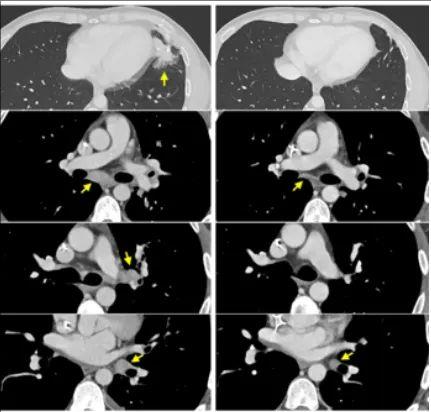

患者一

转移性直肠癌,左肺术后局部复发和纵隔淋巴结消退。

患者二

转移性结肠癌患者,支气管镜记录的右肺淋巴管炎受累(顶部,轴向)、腹膜后淋巴结和肝周肿瘤(中和底部,冠状方向)的消退。

患者三

转移性直肠癌患者的肝转移、门管淋巴结和多个肺转移的消退。